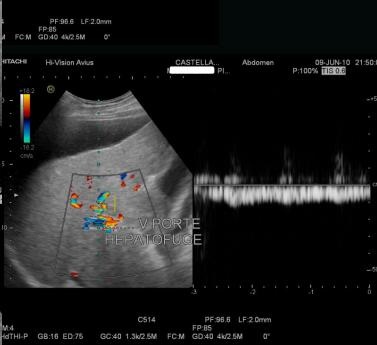

Image radiologique

d'une cirhose du foie : Aspect du veine porte au

arcade portal a diametre de 12mm |

Même cas de cirrhose du foie

: Ce flux dans cette cas est moins de

15cm/s et reverse ( flux inverse ). |